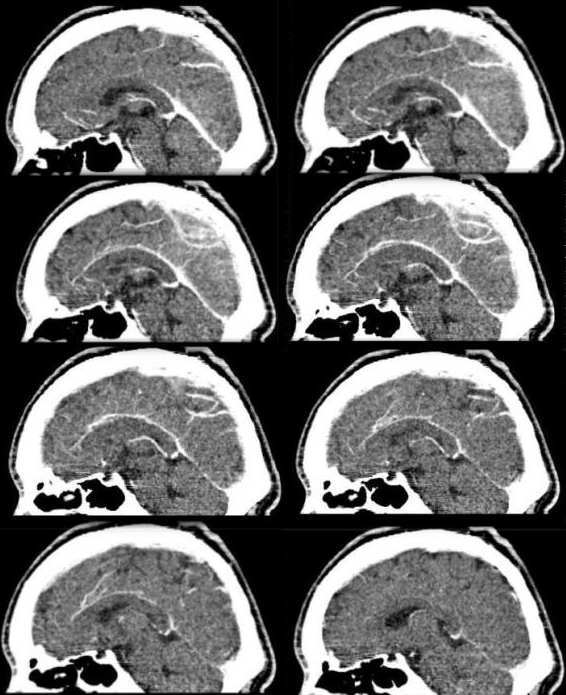

2:矢状位+c:矢状窦还没强化完全,顶部迂曲的血管网已经强化良好,强化速度明显快。靠近上矢状窦并可见迂曲增强的小团状血管影

3:矢状cta:顶部血管强化程度明显强于正常脑血管,呈迂曲不规则状。

综上考虑:顶部脑血管畸形以avm可能性大。并两侧顶叶局限性缺血性脑萎缩

顶部颅板下见弧形走行粗大血管影,明显强化,内见迂曲血管及脑实质影,其内脑实质较周围脑实质强化为著,周围未见水肿征象。轴位片未见明显异常。cta示顶部迂曲血管影增多、增粗,以左侧尤为明显。考虑脑血管畸形可能性大。本例需与以下疾病鉴别:①海绵状血管瘤:病灶局限,内可见斑点状钙化而不可见脑实质影,强化时间较常。②硬膜外血肿:边界清晰,内部不见血管影,周围不见异常血管。